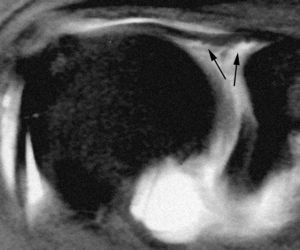

ALPSA (anterior labroliamentous periosteal avulsion)

Al igual que en el apartado anterior, existe también una separación de LG junto con la cápsula y el periostio, pero a diferencia de las lesiones de Bankart o Perthes, el LG se desplaza hacia dentro, por detrás del borde de la glenoides18 (fig. 12). La lesión de ALPSA puede cicatrizar por sinovialización (fig. 12), pero continúa siendo de carácter inestable.

Fig. 12.--ALPSA (anterior labroliamentous periosteal avulsion) agudo (A) y crónico (B). Nótese la separación del labio glenoideo y su desplazamiento posterior y medial por detrás del reborde glenoideo (flecha en A). En una fase crónica el labio glenoideo no se distingue como una estructura separada, sino como un engrosamiento de la unión entre el labio, la cápsula y el periostio (flecha en B).